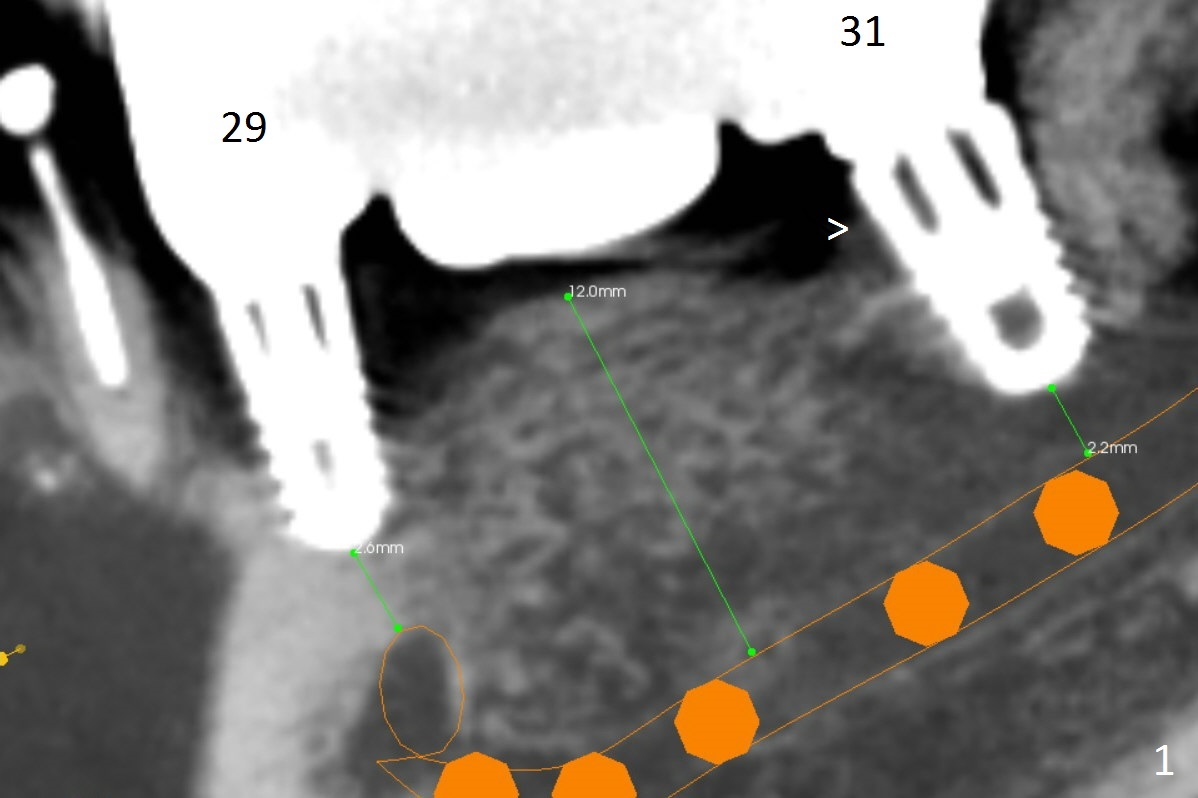

A 64-year-old woman has had sign of periimplantitis at #29 (Fig.1 (CBCT sagittatl section)) in the last 3 years. It appears that the implant is buccally and superficially placed (Fig.3 (coronal section)). Although RCT at #28 is incomplete (Fig.2), there is no symptom or sign of active infection; no treatment will be rendered.

Immediately post implant removal at #29, a 3x10(4) mm 1-piece implant will be placed as lingual as possible (Fig.3). In fact the apical portion of the implant will be lingual to the Mental Loop (Fig.3 orange).

The mesial (Fig.1 >) and lingual (Fig.5 <) threads of the implant at #31 appear to be further bone graft to prevent periimplantitis.